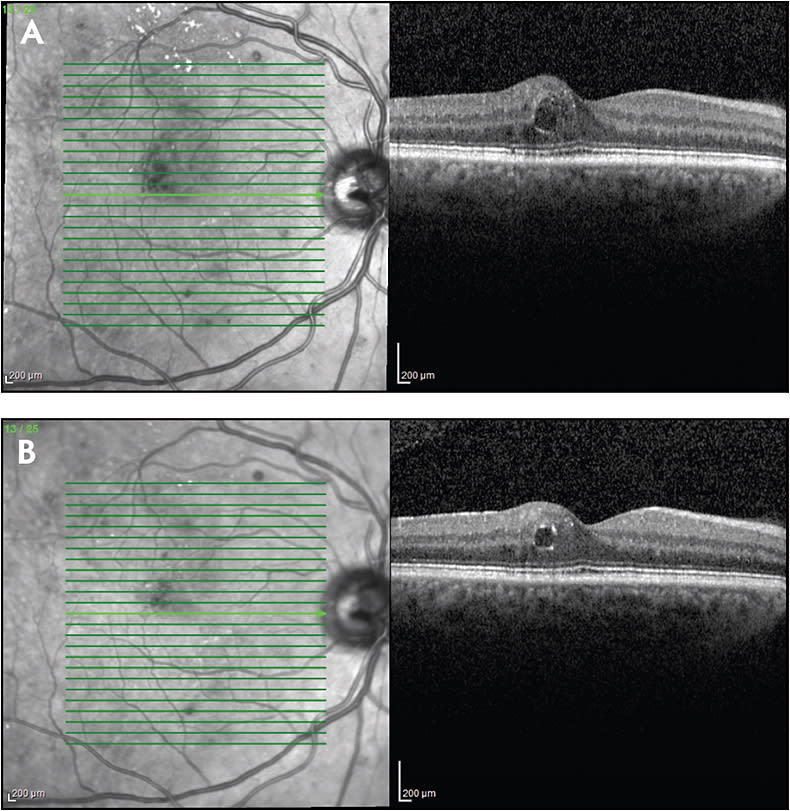

The concept of “response” to pharmacotherapy for DME is complex. Macular thickening is typically measured with optical coherence tomography (OCT), but the relationship between central subfield thickness (CST) and best-corrected visual acuity (BCVA) is not straightforward. Some patients achieve excellent anatomic results with treatment but do not achieve corresponding visual acuity (VA) improvement; this disparity may be due to macular ischemia, photoreceptor damage due to longstanding edema, or other factors. Disorganization of the inner retinal layers on spectral-domain (SD)-OCT has been reported to be associated with worse baseline BCVA and less favorable response to treatment.1,2 Alternatively, some patients with persistent DME may maintain or even improve in BCVA.

Observation, along with encouragement of tighter control of metabolic factors, may be considered in certain patients (Figure 1). These patients may include asymptomatic patients, patients with good presenting BCVA, and patients with non-center-involved DME.

Currently available corticosteroids include the dexamethasone delivery system (Ozurdex; Allergan), the fluocinolone acetonide insert (Iluvien; Alimera), and off-label triamcinolone acetonide. When initiating corticosteroid therapy, the preferred options are the dexamethasone delivery system (which is FDA approved for DME) or intravitreal triamcinolone (which is used off label for DME) due to their relatively short durations of action (approximately 3 months) (Figure 3). Triamcinolone is less expensive, somewhat easier to inject, and may be associated with less patient discomfort than the dexamethasone delivery system, which comes packaged in a proprietary injector with a larger needle (22 gauge) than is generally used to inject intravitreal triamcinolone.